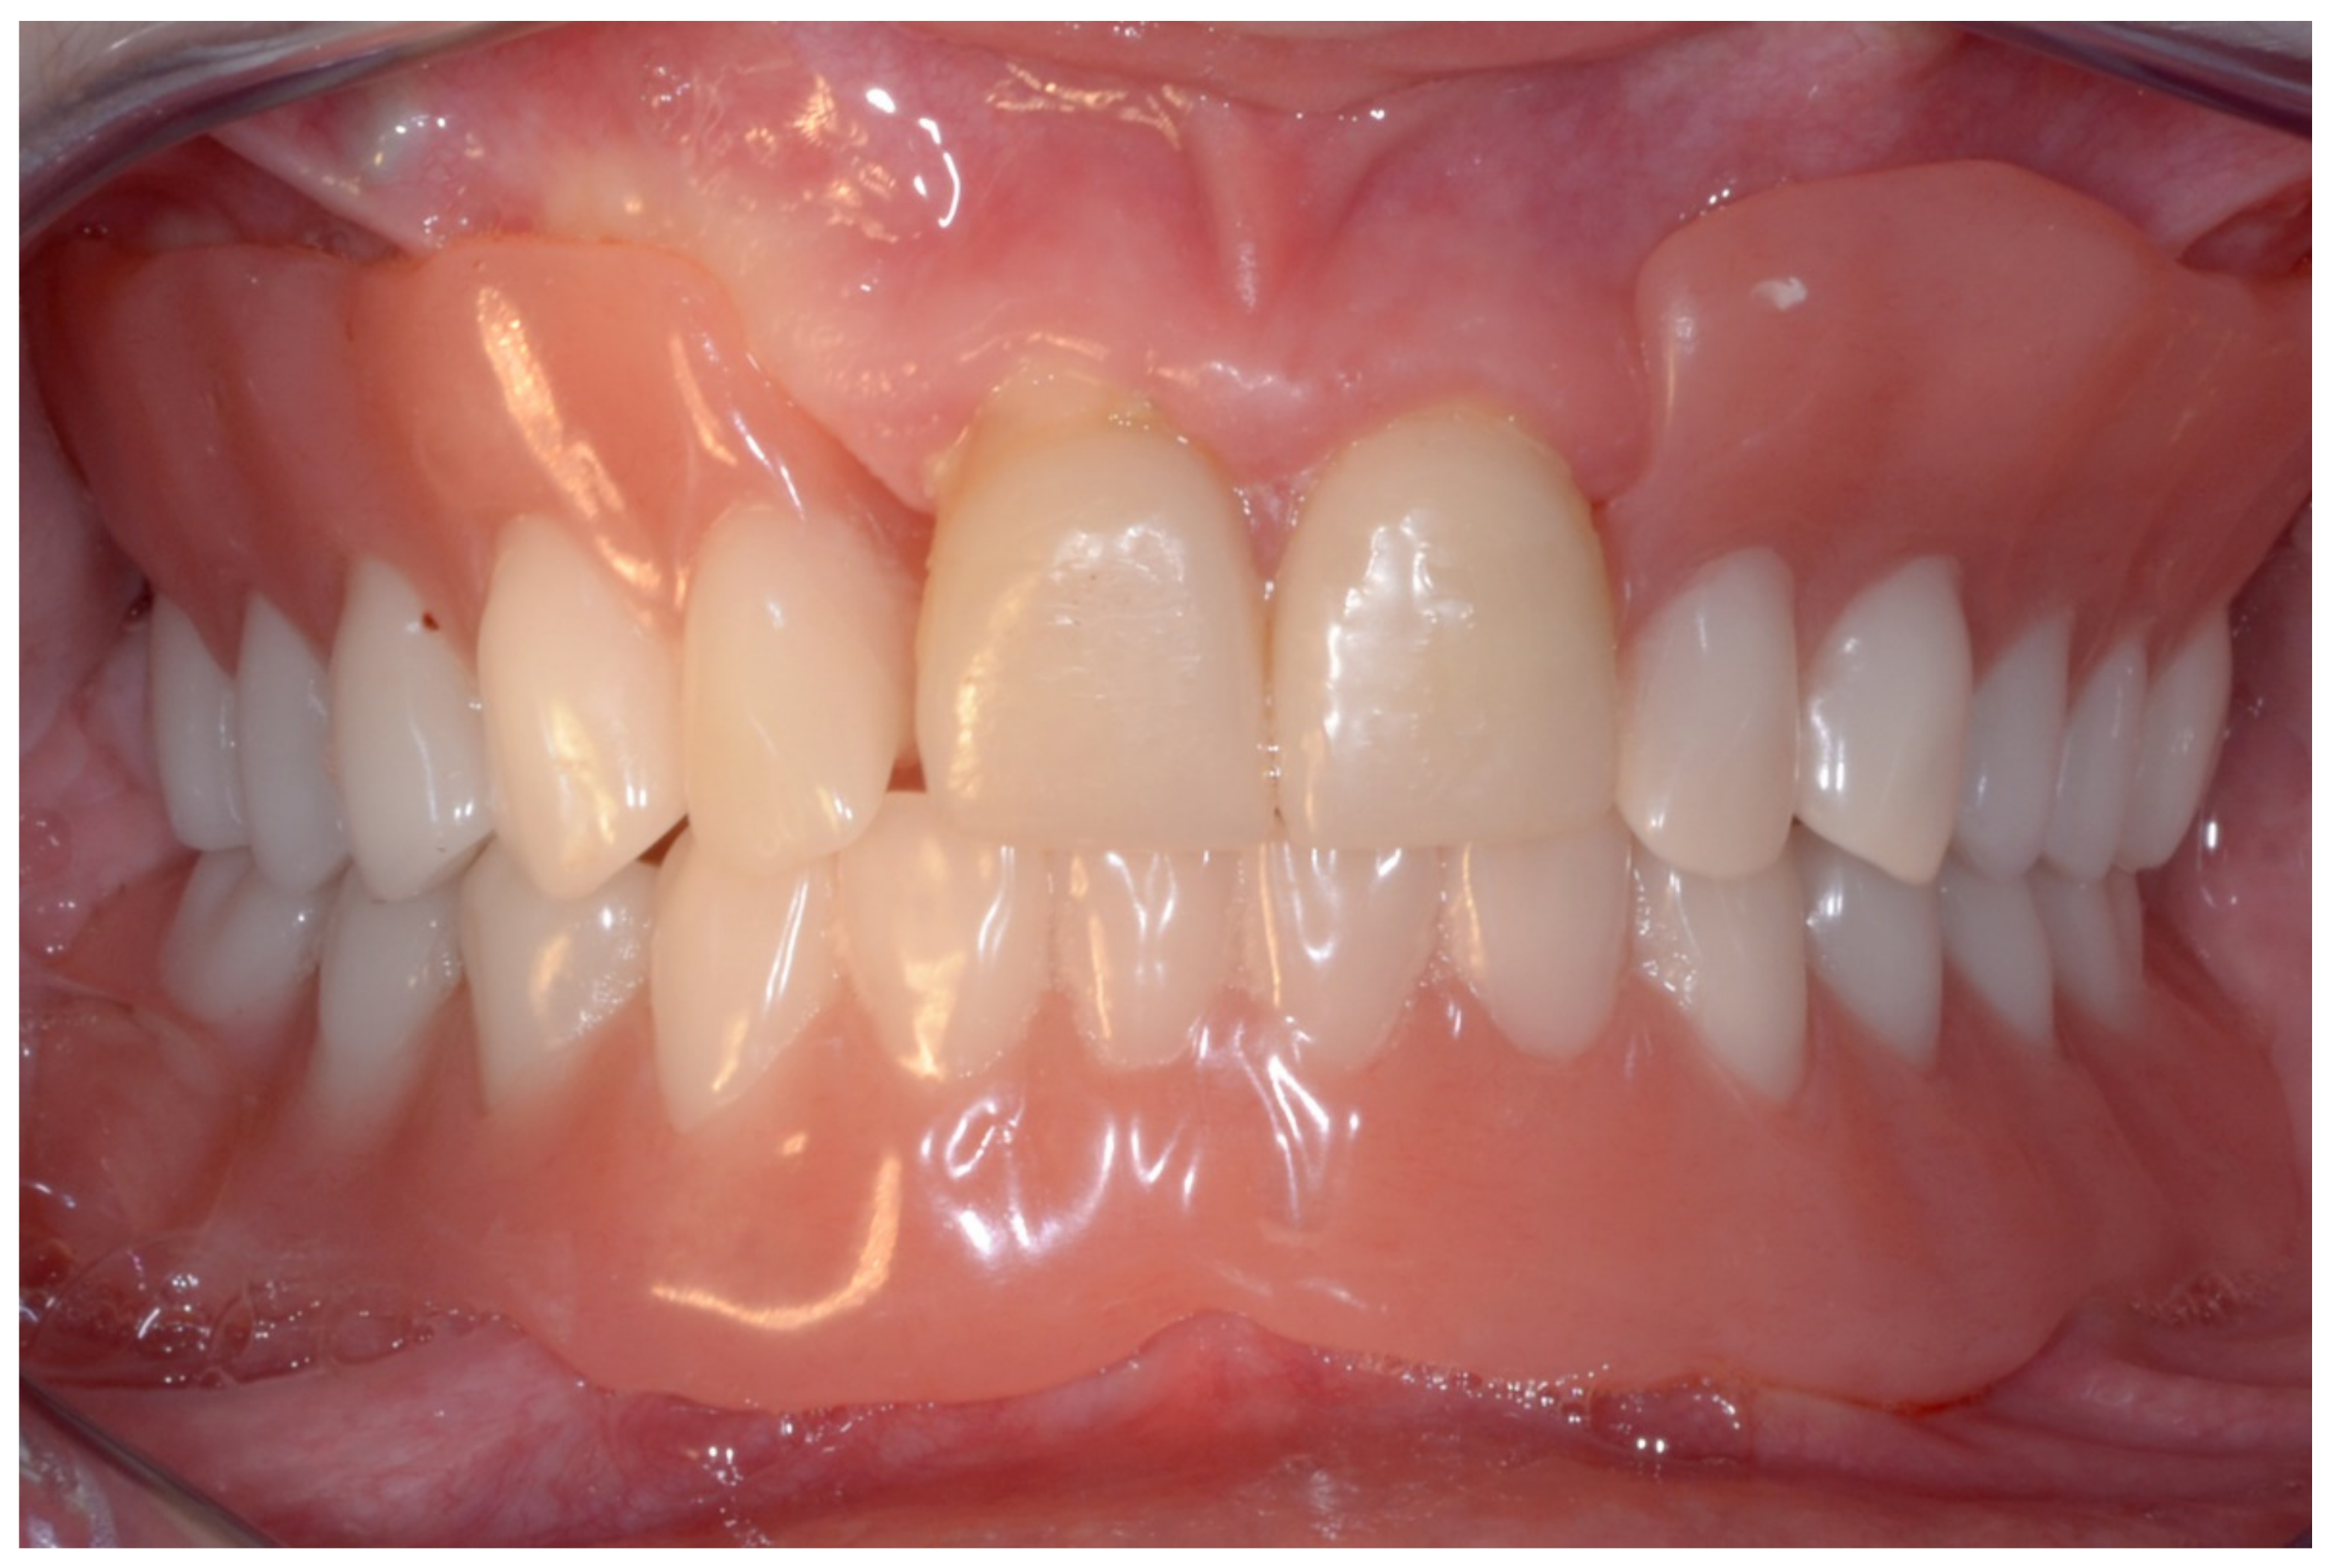

6.1.5. Postoperative (5-Years Follow-Up) Documentation: